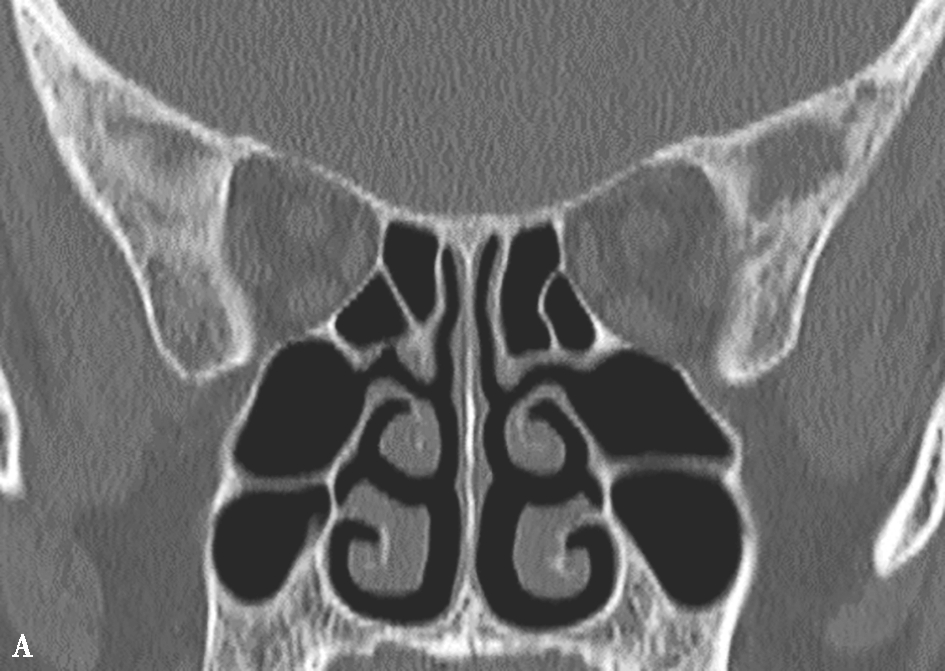

鼻丘气房位于筛漏斗的前上部,与泪骨、上颌骨、筛骨、额骨、鼻骨关系密切。是由筛漏斗直接发展而来。鼻丘气房通常位于额窦底的前部,构成额隐窝的前壁,大小不一,过大、过多可妨碍额窦引流,引起额窦炎。鼻丘气房和钩突眶内壁附着点之间的关系非常密切。当钩突与眶内壁没有附着点时,鼻丘气房不存在;当钩突与眶内壁仅有一个附着点时,鼻丘气房存在;当钩突与眶内壁有两个及以上附着点时,形成上下两个气房,在冠状面观察,偏下的气房称为鼻丘气房,偏上的气房称为额气房,两者内壁均由钩突构成(图1-3-1)。

图1-3-1 鼻丘气房及额气房CT解剖

A~C.鼻丘气房(五角星),额气房(星),钩突(白箭),筛骨纸板(箭头)